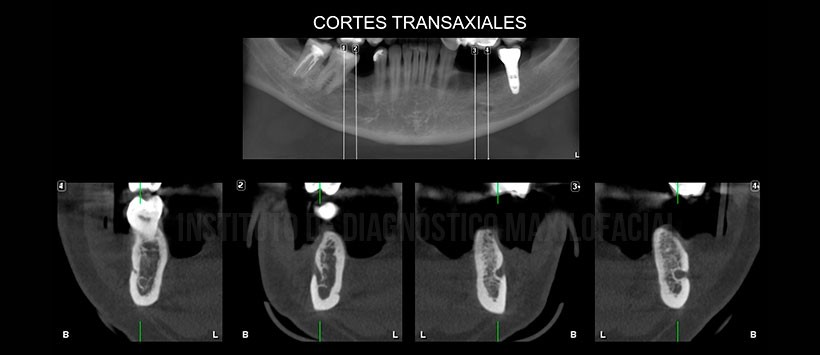

Sin embargo en la evaluación mediante tomografía volumétrica de haz cónico (Figura 2 y Figura 3) se evidencio, que en ambas zonas parasinfisiarias, la presencia de dos agujeros mentonianos en ambos lados con desembocadura en la tabla ósea vestibular.

En las reconstrucciones 3D (Figura 4, Figura 5 y Figura 6) se pudo evidenciar dichas variantes anatómicas del agujero mentoniano de manera ilustrativa así como el recorrido por parte del nervio dentario inferior.